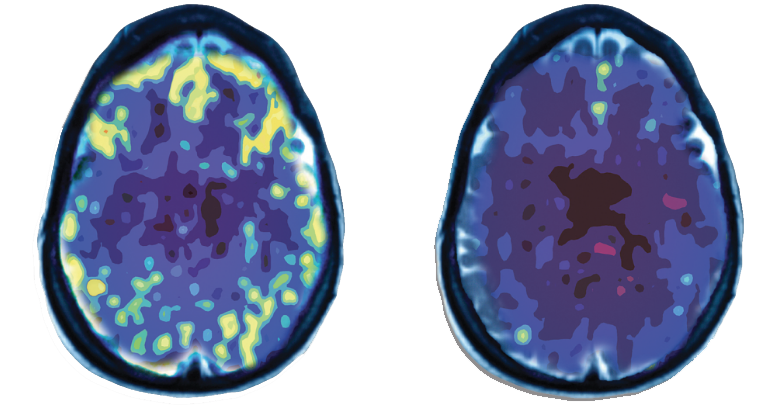

PET Scan: Brain Activity Levels

The PET images here show the differences in brain activity levels between a non-depressed brain (left) and a brain with major depression (right). Note the area in the front of the brain (top of the images) are much more active in the brain without depression. This area is known to be involved in mood regulation. Another region known to be involved in mode regulation is deep in the center of the brain. Note the brain with depression has very low activity compared to the normal brain in the central region.21

TMS Therapy has been shown to improve the activity levels in both the frontal and central areas of the brain.21

Non-Depressed Brain

Depressed Brain

A PET scan measures vital functions such as blood flow, oxygen use and blood sugar (glucose) metabolism.21